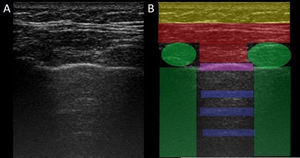

LUS is performed through the intercostal spaces with the probe perpendicular to the thoracic surface in a longitudinal position, resting its proximal and caudal ends on the upper and lower ribs that delimit the intercostal space. The bony landmarks are the bony costal ridges. The visceral and parietal pleura are depicted as a single line located 0.5 cm below the costal ridges, called the "pleural line". The appearance of the 2 costal images with the intervening pleural line is known as the "bat sign" (Fig. 1).

Image of normal ultrasound performed in a healthy patient, obtained with GE Logiq 3 equipment with a 10–14 MHz multifrequency linear transducer, in the third right intercostal space, with the patient in the supine decubitus position and the transducer in longitudinal direction. A) Original image. B) Skin and subcutaneous cellular tissue highlighted in yellow; in red, myofascial layers; in green, ribs and the acoustic shadow they generate; in purple, pleural line, and in blue, A lines.

In the normal lung, because of the large difference in acoustic impedance between the air and the surrounding soft tissues, the pleura behaves as an almost perfect reflector of the ultrasound waves; it produces multiple reverberation phenomena between the pleural line and the probe. The pleural line is visualised as hyperechoic, shiny, thin, and regular, with smooth sliding motion synchronous with respiration called "lung sliding". Below the pleural line there are characteristic horizontal artefacts: "A-lines", which are replicas of the pleural line arranged equidistant from each other due to ultrasound reverberation at the pleural line and artefacts resulting from the myofascial layers of the chest wall due to minor reverberation phenomena and mirror effects.24